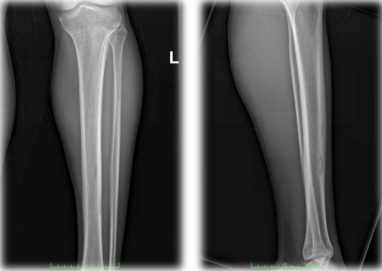

Radiographs taken in the ED demonstrated a lesion with subtle sclerosis in the anterolateral midshaft of the left tibia (Figure 1). A CT scan of the left leg revealed a focal cortical lesion with central calcification suggestive of an osteoid osteoma in the anterior aspect of the left mid-tibial shaft. Proximal to this lesion, another similar lesion with a periosteal reaction was noted just distal to the tibial tuberosity (Figures 2-4).

Figure 1a: This preoperative X-ray shows the AP view of the left tibia, revealing areas of cortical thickening indicative of osteoid osteoma. The imaging is crucial for assessing the location and extent of the lesion before surgical intervention.

Figure 1b: This preoperative X-ray shows the lateral view of the left tibia. The image highlights the cortical thickening and possible nidus characteristic of osteoid osteoma. This view complements the anterior view by providing additional information on the depth and precise localization of the lesion.